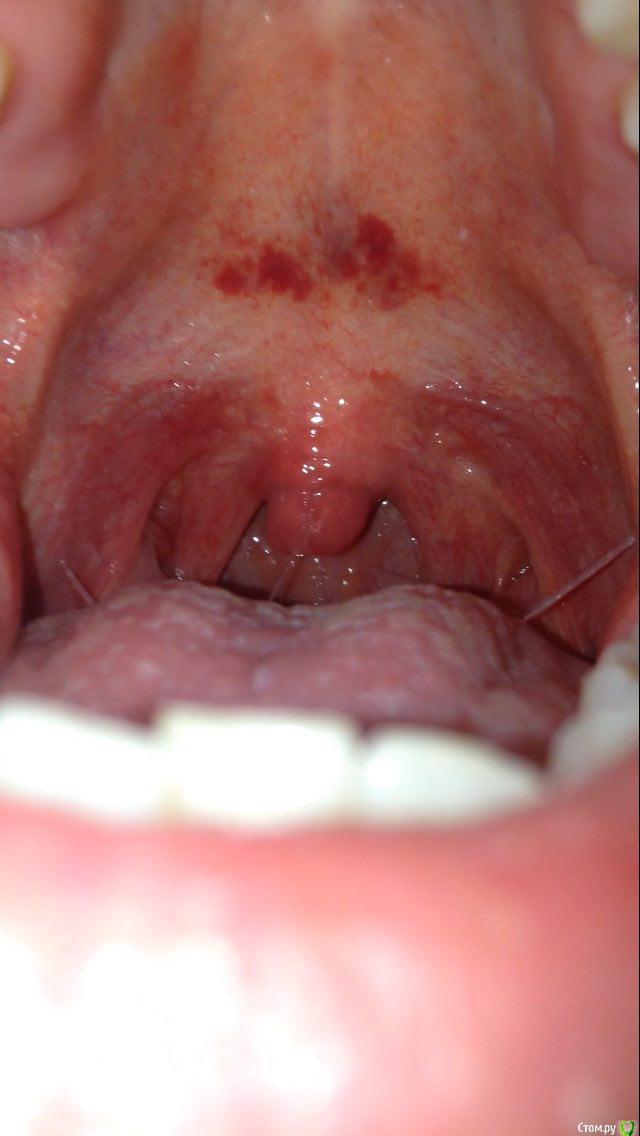

iantoshkai Опубликовано 3 января, 2018 Поделиться Опубликовано 3 января, 2018 (изменено) Незнаю что это. Прикрепил фото, подскажите, на что похоже Изменено 3 января, 2018 пользователем iantoshkai Ссылка на комментарий